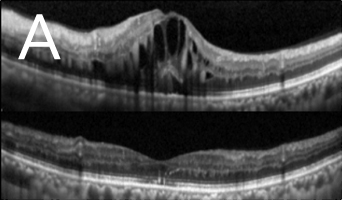

近视超过600度的人士眼球拉长的情况非常严重,黄斑点亦被拉扯变薄。再加上不正常的玻璃体和黄斑点视网膜前膜增生之牵引,导致黄斑点神经组织裂开,甚至丧失视力。如未能及早施行适当治疗,黄斑点裂损有可能进一步恶化,导致黄斑点穿孔和黄斑点视网膜脱落。利用光相干性断层造影可及早发现并作出准确的诊断(图3)。治疗方法是施行扁平部玻璃状体切除术,移除凹前表质玻璃体,并进行气体和液体交换,治疗可治愈大部份病人的黄斑点凹位,而大部份病人在手术後亦无须保持俯卧。

![]() ![]() 图3:光相干性断层造影(OCT):(A)发现大量黄斑点裂损,并有视网膜黄斑点凹位脱落迹象,且在黄斑点凹位附近发现不正常的玻璃体牵引(箭头所指位置)。(B)手术後六个月黄斑点裂损的情况大有改善,减少视网膜黄斑点脱落的幅度。 |